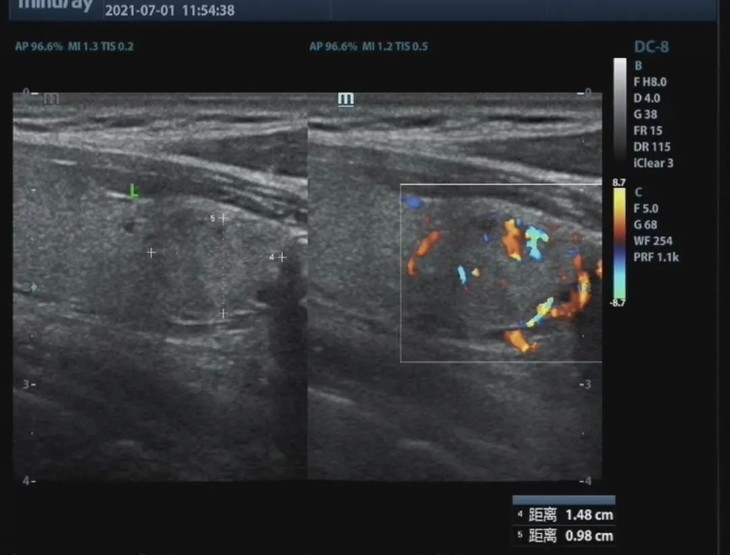

隔天,我请了病假,办理了住院,医生让我在术前最后做一次颈部彩超。

「哦。」他用探头找到了那枚葡萄大小的滤泡肿瘤,端详了一会显示器中超声信号组成的图像,冷不丁说「我觉得你这个情况,可以直接走。」